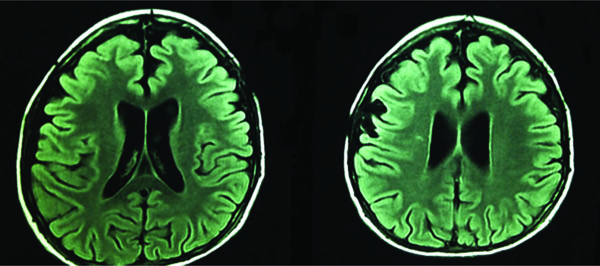

Brain magnetic resonance imaging showed the ventricular system in the midline mild bilateral ventricular dilation, an increase in supratentorial volume with no associated sub-ependymal edema, slightly decreased overall encephalic volume for the patient’s age and no causes of intracranial hypertension like tumors or hematomas (Fig. 3).

Brain magnetic resonance imaging, axial views.